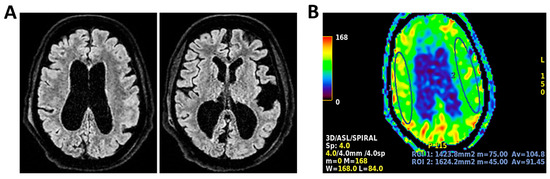

Figure 10.

MRI of patient 5 group 2. A 67-year-old woman with schizophrenia presented to the ER with lethargy and vomiting, following 10 days of fever and dry cough treated ineffectively with Medrol and Cefditoren. Brain CT showed a left temporoparietal hypodensity (sequela) and supratentorial ventricular dilation without midline shift. The lumbar puncture was positive for Listeria monocytogenes (FilmArray). Due to neurological deterioration (GCS 7), she was transferred to the ICU. On day 2, TCCD showed PI values of 1.65 (right) and 1.89 (left), indicating increased cerebral vascular resistance without clear signs of intracranial hypertension. (A) 3D axial FLAIR shows marked and diffuse atrophy of the brain tissue, more pronounced in the left hemisphere where some areas of enlargement of the cerebrospinal fluid spaces are observed, more prominent in the parietal region, and diffuse dilation of the supraventricular system, particularly in the occipital horns. (B) Perfusion study reveals minimal asymmetry in cerebral perfusion values sampled at the level of the semioval centers. Blue circles indicate the ROI used for quantitative CBF analysis.

The remaining two patients in this group experienced poor outcomes. One was diagnosed with progressive multifocal leukoencephalopathy (PML) due to JC virus and presented with a right-dominant perfusion asymmetry and elevated right-sided PI (1.50). MRI revealed extensive subcortical and infratentorial lesions, including the brainstem (Table 3 and Figure 9).

The second patient, affected by L. monocytogenes meningoencephalitis, showed bilateral elevation of PI (1.65 and 1.89) and significant CBF asymmetry (right CBF: 105 mL/100 g; left CBF: 91 mL/100 g) (Table 3 and Figure 10).

Both patients died by day 28. Notably, these two cases demonstrated a mismatch between regional perfusion and vascular impedance, consistent with cerebrovascular dysregulation and loss of autoregulation.